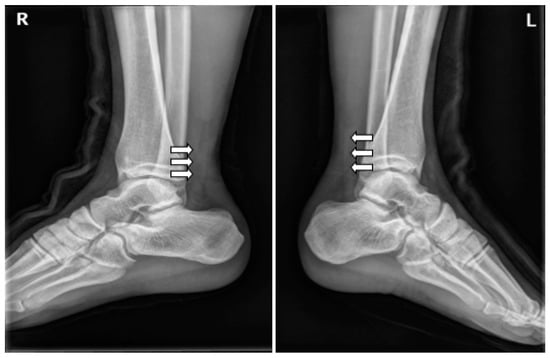

At the time of admission, the Thompson squeeze test was positive in both ankles, and digital exploration revealed dimpling 6 cm superior to the calcaneal tendon attachment site. Preoperative ankle radiographs showed no abnormality in the bone or surrounding soft tissue, other than the loss of Kager’s triangle (Figure 2). MRI confirmed the diagnosis of bilateral AT rupture (Figure 3).

Figure 3. Preoperative sagittal magnetic resonance images of both ankles show rupture of the Achilles tendons (white arrow).